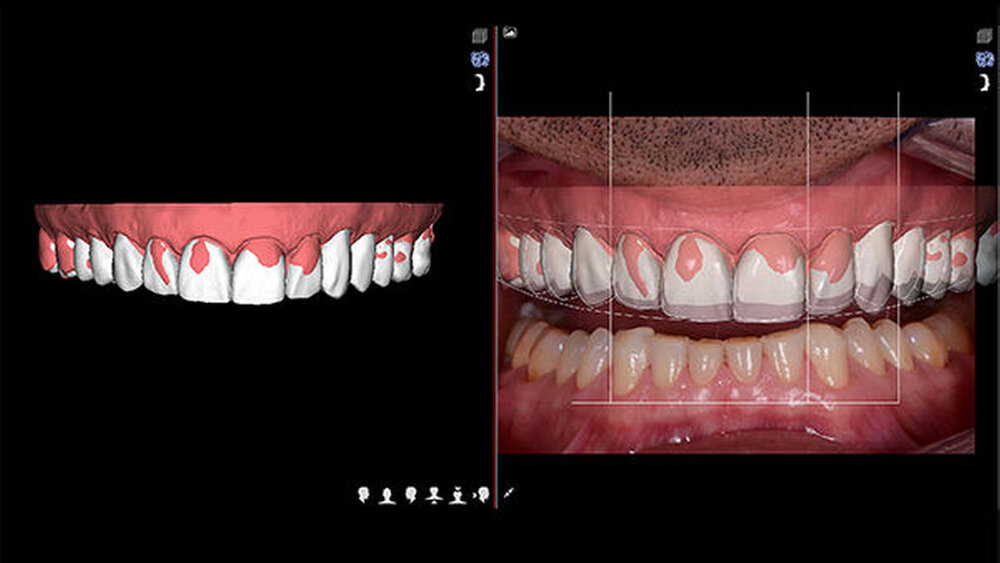

Vier weitere ergänzende Videos wurden für die funktionale, strukturelle und Gesichtsanalyse aufgenommen: ein Gespräch über die Erwartungen des Patienten, ein 180º-Phonetikvideo, ein intraorales funktionales und ein intraorales strukturelles Video mit Lippen-Wangen-Halter (Abb. 5). Die Informationen wurden an das DSD-Labor übermittelt. Das Hauptziel der DSD-Technik besteht darin, die Fotos der drei Ansichten (okklusal, frontal und 12 Uhr) mit einem digitalen Lineal in Einklang zu bringen, um mithilfe der Videoanalyse die Proportionen des Lächelns (Smile Frame) herzustellen.

Anschließend wurde der Smile Frame unter Berücksichtigung der Gesichtssymmetrie wie folgt erzeugt: digitaler Gesichtsbogen, Form und Position der Lachkurve, Breitenermittlung anhand der RED-Korrelation, Längenproportion, Gingivakurve, Papillenkurve, Amorbogen und Kieferkurve. Die 2D-Proportionen des Lächelns wurden in der CAD-Software in ein digitales 3D-Simulationsmodell überführt. Die so erstellte 3D-Datei im STL-Format wurde an einen Drucker übermittelt, der das Modell mit dem neuen Design erzeugte. Anschließend wurde es zur Herstellung einer Matrize aus Bis-Acryl (Structur; VOCO) für das Motivations-Mock-up verwendet (Abb. 6). Im neuen Modell wurde die Vertikaldimen‧sion (VD) erhöht, weshalb der Patient das Mock-up zwei Wochen testete, um zu prüfen, ob die neue Bisshöhe den Erwartungen entsprach. Die Bisserprobung ergab keine Stabilitätsprobleme, und der Patient fühlte sich damit wohl, weshalb kein Anlass für eine weitere Deprogrammierung des Aufbisses und die Definition einer neuen zentrischen Relation bestand. Mit dieser neuen VD fühle sich der Patient wohler und hatte keine Schmerzen im TMG. Der Behandlungsplan wurde vorgestellt, aber aus finanziellen Gründen wollte der Patient die Behandlung nicht fortsetzen.